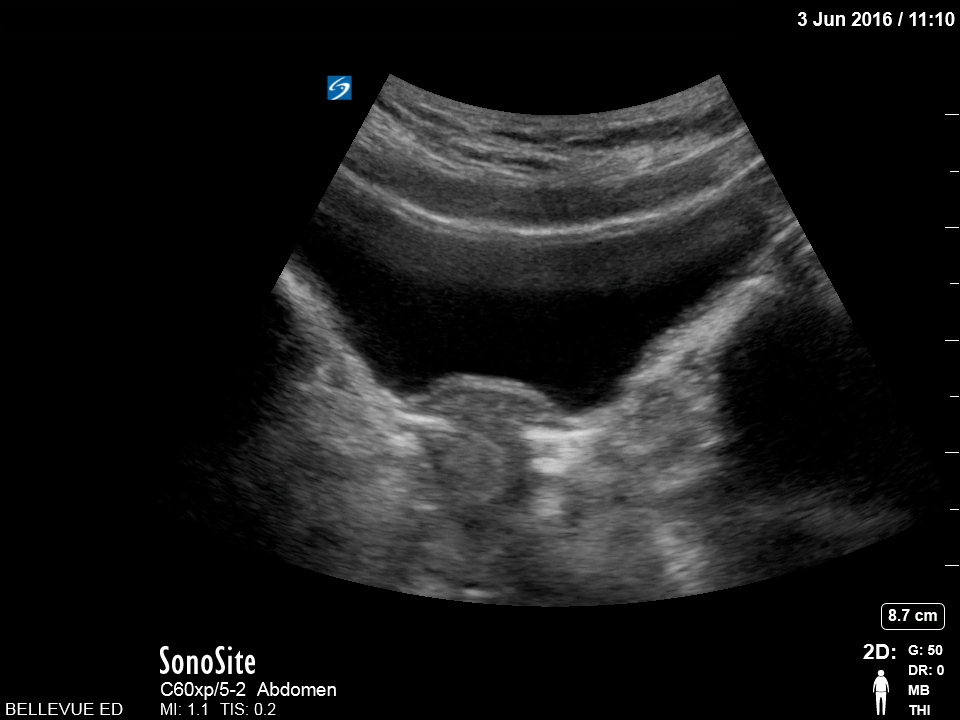

Transabdominal Uterus (transverse) Teal: Bladder, Pink: Uterus Images: Dr. Lindsay Davis, Dr. Hannah Kopinski. Image Editing: Michael Amador and Dr. Matthew Riscinti